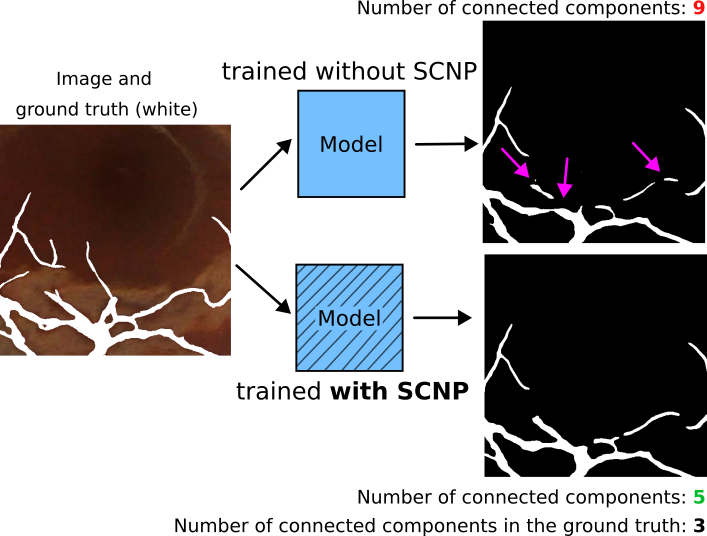

In image segmentation, performance is typically measured with pixel-level metrics, like Dice coefficient and accuracy. However, these metrics alone tell very little about image segmentation quality. Topology accuracy (i.e., the accuracy in the number of connected components and holes between the prediction and the ground truth) is a good indicator of image segmentation quality, particularly when the downstream tasks rely on precise counts of objects or structures and their connectivity. For example, the connectivity of the roads in satellite images or in blood vessels is more important than their accuracy at the border.

SCNP improved topology accuracy without deteriorating Dice coefficient.

Qualitative results.